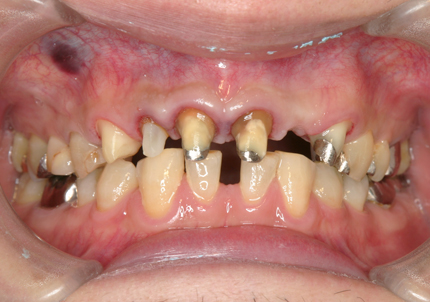

1.初診時口腔内写真(2014年6月)

2.左上2番 矯正的抜歯(2014年9月)

主訴の左上2番う蝕歯は、抜歯後歯頚線を揃える目的で矯正的挺出の後に抜歯する